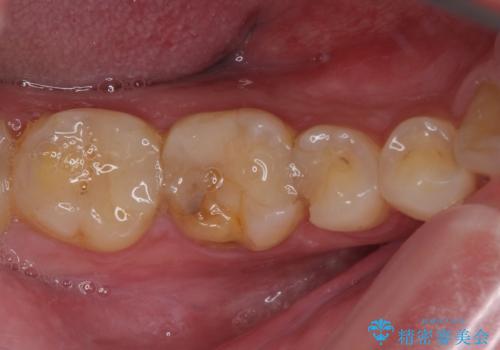

- 奥歯が欠けてしまったとのことで来院された患者様です。

おそらく歯が欠けて、装着されていた銀歯が外れてしまったと思われましたが、患者様はあまりはっきりとは覚えていないとのことでした。

咬合力が強いため、強化セラミッククラウンでの補綴治療を行うこととしました。